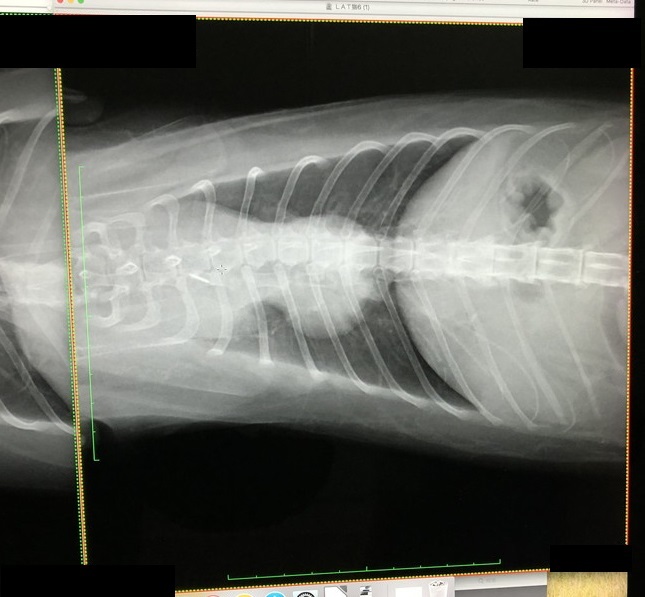

朝起きると嘔吐を繰り返しており、動物病院へ。

ウイルス性の胃腸炎とのことで、嘔吐止め、点滴の処置を受けましたが、1週間ほど経っても食欲が戻らず、再び受診したところ、血液検査、レントゲン、エコー、細胞診などの検査をして、悪性縦隔リンパ腫の可能性が高いことがわかりました。

また、この時の検査で白血病に罹患していることもわかりました。

■診断、治療

まだ4歳の若さですが、悪性縦郭リンパ腫、低分化型とのことで、進行も早いようです。

縦隔リンパ腫は、左右の肺を繋ぐ場所にできる腫瘍で手術で取り除くのは難しいそうです…

手術のほか、放射能治療も不可のようで、治療は抗がん剤の一択しかないとの事でした。

【診断書、初回検査時】

【抗がん剤1回目】

【抗がん剤2回目】

【治療3週目、輸血時】